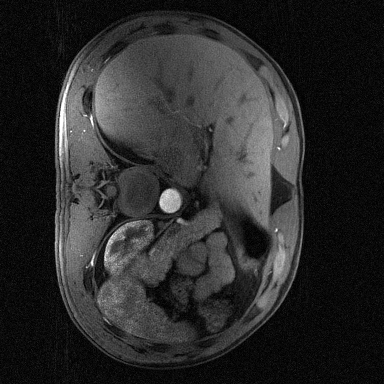

Supervised Deep-Learning (DL)-based reconstruction algorithms have shown state-of-the-art results for highly-undersampled dynamic Magnetic Resonance Imaging (MRI) reconstruction. However, the requirement of excessive high-quality ground-truth data hinders their applications due to the generalization problem. Recently, Implicit Neural Representation (INR) has appeared as a powerful DL-based tool for solving the inverse problem by characterizing the attributes of a signal as a continuous function of corresponding coordinates in an unsupervised manner. In this work, we proposed an INR-based method to improve dynamic MRI reconstruction from highly undersampled k-space data, which only takes spatiotemporal coordinates as inputs. Specifically, the proposed INR represents the dynamic MRI images as an implicit function and encodes them into neural networks. The weights of the network are learned from sparsely-acquired (k, t)-space data itself only, without external training datasets or prior images. Benefiting from the strong implicit continuity regularization of INR together with explicit regularization for low-rankness and sparsity, our proposed method outperforms the compared scan-specific methods at various acceleration factors. E.g., experiments on retrospective cardiac cine datasets show an improvement of 5.5 ~ 7.1 dB in PSNR for extremely high accelerations (up to 41.6-fold). The high-quality and inner continuity of the images provided by INR has great potential to further improve the spatiotemporal resolution of dynamic MRI, without the need of any training data.